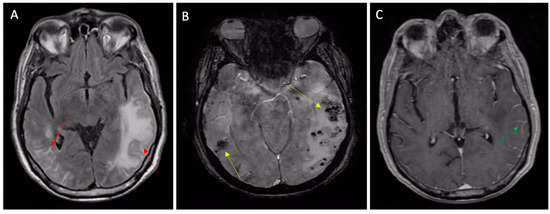

2.3. Diagnosis of CAA

- Charidimou, A.; Boulouis, G.; Frosch, M.P.; Baron, J.C.; Pasi, M.; Albucher, J.F.; Banerjee, G.; Barbato, C.; Bonneville, F.; Brandner, S.; et al. The Boston criteria version 2.0 for cerebral amyloid angiopathy: A multicentre, retrospective, MRI-neuropathology diagnostic accuracy study. Lancet Neurol. 2022, 21, 714–725. [Google Scholar] [CrossRef]

2.4. Differential Diagnosis (Table 3)

| Clinical Condition | Main Radiological Characteristics |

|---|---|

| Hypertensive microangiopathy | Hemorrhages are typically located in the basal ganglia, in the bridge, and in the cerebellum; they are not associated with subarachnoid hemorrhage or superficial siderosis. |

| Infective endocarditis | Combination of acute SAH, cSS, CMBs, cortical/sub cortical hematomas, cortical/subcortical abscess, small pial enhancement on post-contrast imaging, ischemic stroke, or focal stenosis on vascular exploration. Note that radiological features can rapidly change under antibiotics. |

| Heart surgery/left-ventricle assist devices | Combination of acute SAH, cSS, parenchymal hematomas, CMBs, cerebral atrophy, or white matter leucopathy. |

| Multiple cavernomatosis | The lesions have a random distribution and size, although the classic cavernous malformations are not distinguishable from CAA-related brain microhemorrhages. Often, the lesions have the typical “popcorn” appearance. |

| Hemorrhagic metastases | Lesions have a variable size and can often be larger than micro-hemorrhages. They present contrast media enhancement. |

| Widespread axonal damage | Lesions are typically located at the junction of the gray-white substance, in the corpus callosum and, in the most serious cases, in the brain stem. |

| Neurocysticercosis | Calcific nodular component visible on CT or MRI in susceptibility-weighted images, random distribution. |

| Fat embolism syndrome | It has a typical “starfield” presentation. Lesions also show limited diffusion in diffusion MRI sequences. |

| Radiation-induced vasculopathy | Microemorrhagic foci have a very similar appearance to CAA, but with a distribution limited to the treated area. |